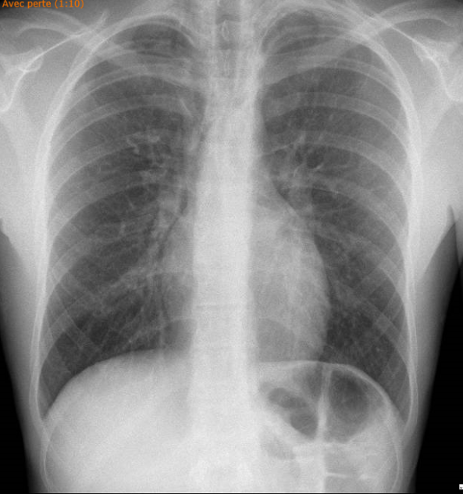

Un patient de 20 ans se présente aux urgences suite à l’apparition d’une douleur cervicale survenue après un éternuement. Il décrit une sensation de clic à la déglutition, sans dyspnée.

A son arrivée aux urgences, il est hémodynamiquement stable avec TA 126/76 mmHg, FC 85 bpm, sat 96% à l'air ambiant, eupnéique et afébrile. L’examen cardiopulmonaire est normal.

Voici sa radiographie du thorax :

Quel est ton diagnostic ?